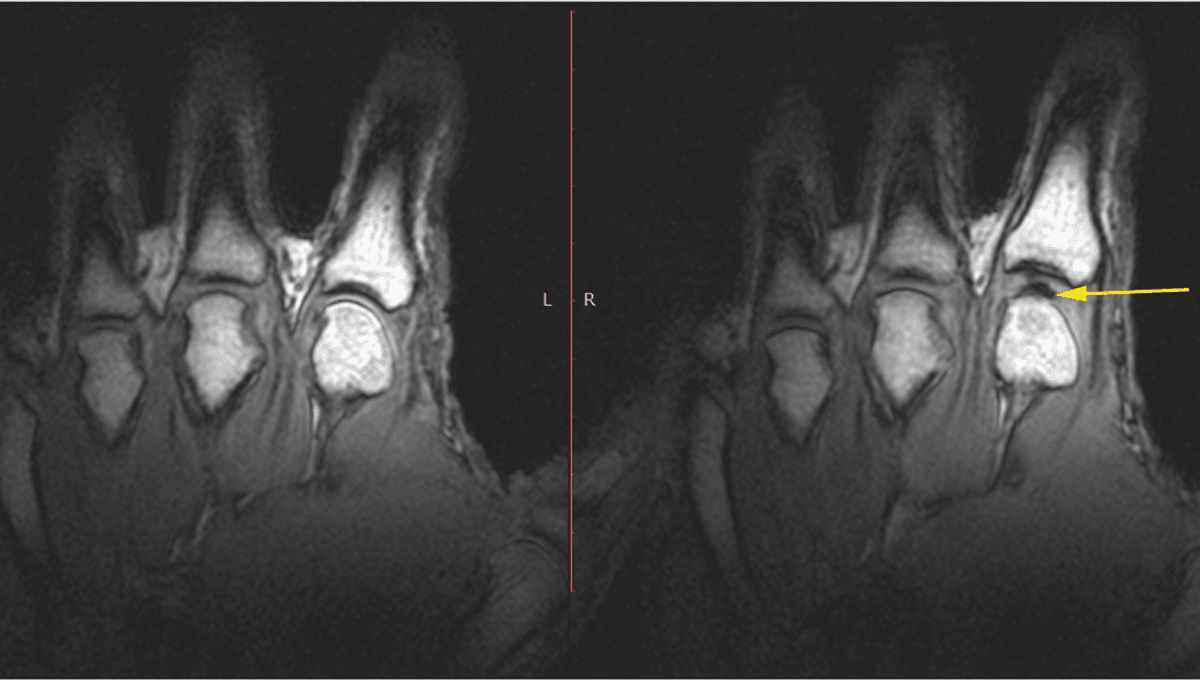

What Is That Horrible Sound When You Crack Your Knuckles?

A sound that launches a thousand unsolicited opinions.